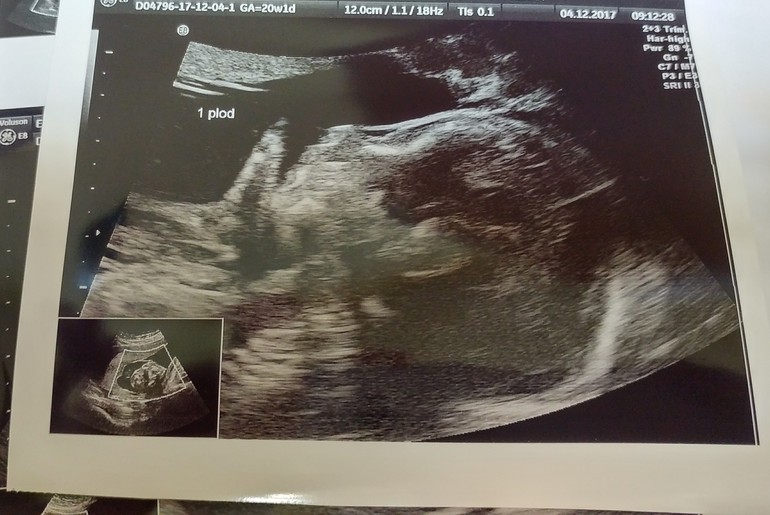

Ну и, конечно, главное событие - это скрининг :) Малыши вели себя довольно спокойно по сравнению с предыдущими узи, наверное были сонные с утра. Сначала лежали параллельно головками вниз, а затем девочка перевернулась и начала дубасить мальчика по лицу пяткой 😆 Доктору даже удалось подловить этот момент на фото 😍

У деток все по сроку, только у девочки длинные руки и ноги, доктор сказала, что это хорошо, просто высокая :) Пока что они по размеру такие же как детки при одноплодной беременности на этом сроке. Шейка ТТТ хорошая, 38-40 мм, закрыта.